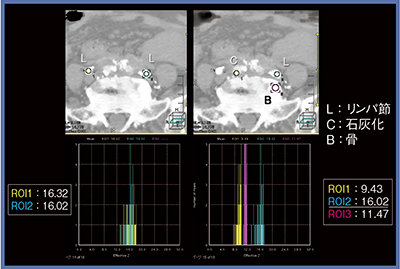

当院では,DECTの物質弁別について,実効原子番号(Effective Z)と電子密度(Electron Density)の検討も行った。当院で使用したリピオドール,ヨード造影剤,ガドリニウム造影剤について体外ファントムで解析を行った結果,実効原子番号と電子密度は図6のとおりとなった。実際に実効原子番号でリピオドールを弁別できるか検討したところ,リンパ管造影ではリピオドールの沈着を表しており,また,リンパ節のリピオドール沈着と石灰化,骨のそれぞれの実効原子番号を見ると,分離は可能だと思われる(図7)。一方,電子密度ではリピオドールと石灰化,骨のプロットが重なる部分があり,弁別は困難だと言える(図8)。

このことから実効原子番号によるリピオドール弁別は可能と思われたが,ROIが小さい小病変では測定が困難で,集積の程度により測定値にバラツキがあり,また,体内測定時のゴールドスタンダードが存在しないという問題がある。

図8 電子密度によるリピオドールの弁別